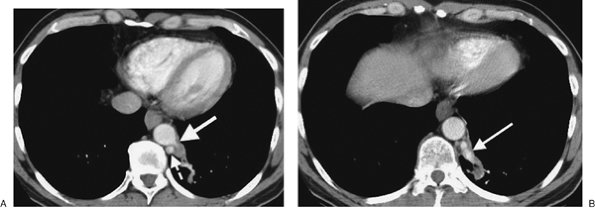

Bronchopulmonary sequestration consists of nonfunctioning lung tissue, usually cystic and often masslike, that has an anomalous systemic blood supply, usually from the aorta, and no normal communication with the tracheobronchial tree. This disorder is classified into two types: intralobar (the more common type) and extralobar (4). Both types occur most commonly in the posterior basal segment of a lower lobe, usually on the left. Intralobar sequestration is contiguous with normal lung parenchyma, has no separate pleural investment, receives arterial supply most commonly from the aorta, has venous drainage most commonly into a pulmonary vein, and is only rarely associated with other anomalies (Figs. 16-2 and 16-3). Extralobar sequestration is related to a hemidiaphragm (usually the left), and it is often situated between the inferior surface of the lower lobe and the diaphragm, or below the diaphragm. It has a pleural investment separate from the rest of the lung; receives arterial supply from the aorta but usually has venous drainage into the systemic venous system (e.g., inferior vena cava, azygos vein, or portal vein); and is often associated with other congenital anomalies (most commonly eventration or paralysis of the ipsilateral diaphragm and left diaphragmatic hernia) (Fig. 16-4). The classic radiographic appearance of pulmonary sequestration is recurrent or persistent abnormal opacity in a lower lobe that never completely clears. The diagnosis can be confirmed by showing the systemic arterial supply, either with magnetic resonance imaging or CT angiography (5). In adults, this disorder is often discovered incidentally.

FIGURE 16-4. Extralobar sequestration. A: CT of a 56-year-old man with persistent abnormal opacity in the left lower lobe on chest radiography shows a vascular structure arising from the descending aorta (solid arrow) and directed toward a mass in the left lower lobe. The hemiazygos vein is prominent (dashed arrow). B: CT at a more inferior level shows a large vein arising from the left lower lobe mass and draining into the hemiazygos vein (arrow). C: Coronal reformatted CT shows a prominent hemiazygos vein (arrow). D: CT at the level of the left atrium shows the hemiazygos vein (solid arrow) crossing the midline posterior to the descending aorta to join the azygos vein (dashed arrow). Surgical resection of the left lower lobe sequestration confirmed the arterial supply and venous drainage.